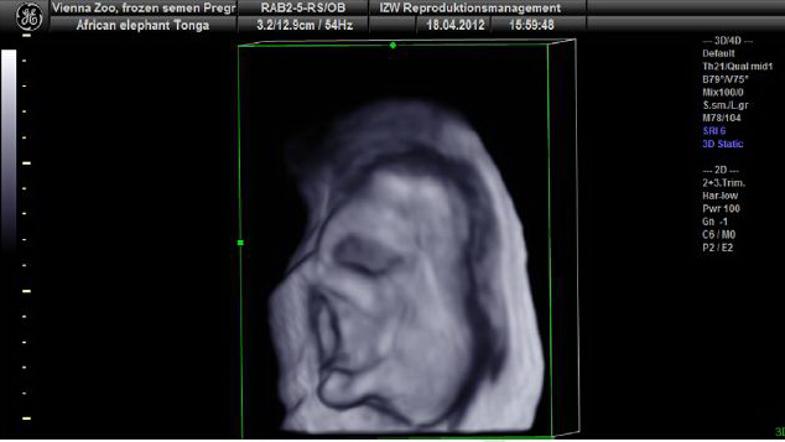

V dunajskem živalskem vrtu so uspešno oplodili slonico. Zarodek je trenutno star devet mesecev.

V dunajskem živalskem vrtu Schönbrunn je uspela oploditev afriške slonice Tonge s semenom samca, ki živi na prostem v Južni Afriki. Gre za prvo uspešno umetno oploditev slona z zamrznjeno spermo na svetu. Zarodek je trenutno star devet mesecev, vendar bo na skotitev mladička treba počakati še kar nekaj časa, saj so slonice običajno breje kar 22 mesecev, so sporočili iz Agencije za stike z mestom Dunaj.

Da so veterinarji lahko pridobili spermo samca, ki živi v južnoafriškem rezervatu Phinda Private Game Reserve, so ga morali najprej uspavati in mu z električnim spodbujanjem odvzeti seme. Novembra lani so na ta način uspešno oplodili 26-letno slonico Tongo iz dunajskega živalskega vrta. Devet mesecev star zarodek je zdaj velik približno 20 centimetrov, spola pa mu še ne morejo določiti.